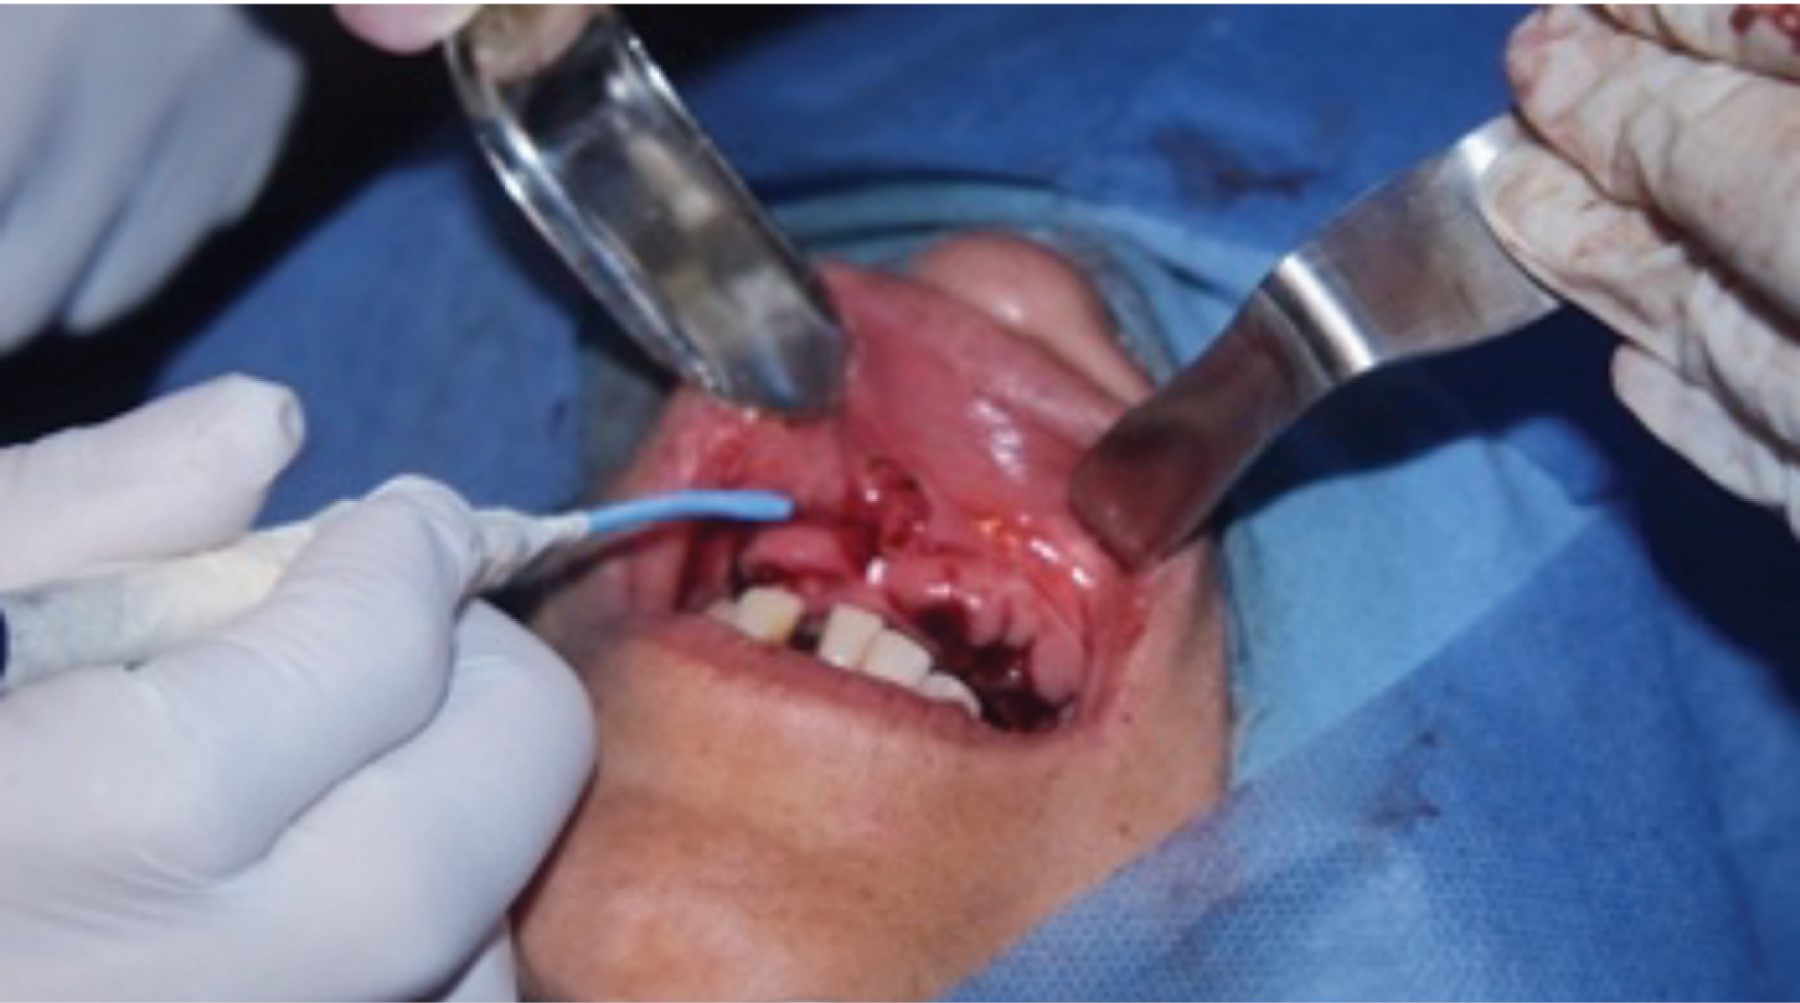

Se realizaron las cirugías preprotésicas, se inició con la arcada superior en la cual se realizaron extracciones múltiples, regularización del proceso y frenectomía del frenillo labial. Al finalizar el acto quirúrgico se colocó acondicionador de tejidos a la prótesis inmediata superior con el fin de producir presión en el proceso alveolar, disminuir la inflamación que produciría la cirugía y acondicionar los tejidos para las prótesis definitivas (Figuras 5, 6 y 7).

Figura 5

Figura 6

Figura 7